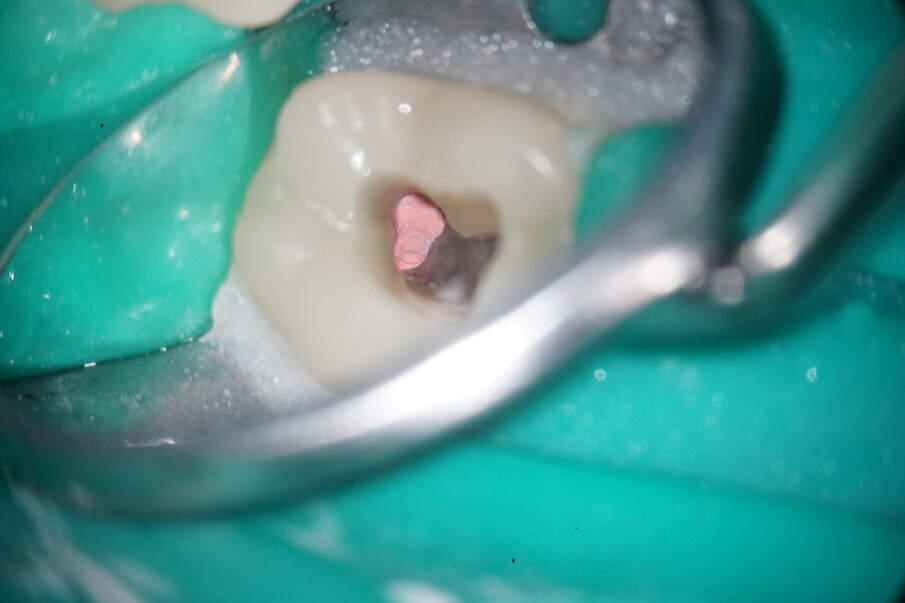

The remaining apical gutta-percha was removed distally using a reciprocating 25/.06 MicroMega One RECI (Fig. 6). Owing to its cross-sectional design, this instrument features high cutting performance, making it ideal for revision treatment.

Fig. 4: Initial situation of distal canals.